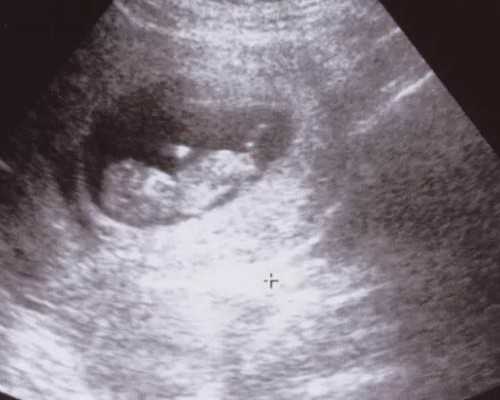

若把胚胎比作种子,那么子宫内膜就是土壤,如果土壤不肥沃,你所播的种子就不会发芽,移植后胚胎就不会着床,试管婴儿就不能成功。子宫内膜容受性的好与差是决定试管婴儿成功的关键因素,而宫腔镜检查就是评估宫腔内环境的一种临床常用的方法。

卵巢储备可以通过窦卵泡计数来评估,需要通过超声观察,以及测量内分泌标志物如FSH,雌二醇,AMH和抑制素B含量,或者采用动态试验,研究卵巢对不同刺激药物的反应。

卵泡存在于卵巢中,包裹着卵母细胞。一个窦阶段的卵泡直径约为2和9毫米,它们的数量能反应关于卵巢储备状态的重要信息。

该测试应在女性月经周期的卵泡期进行,即在月经周期的第3天和第5天之间进行。